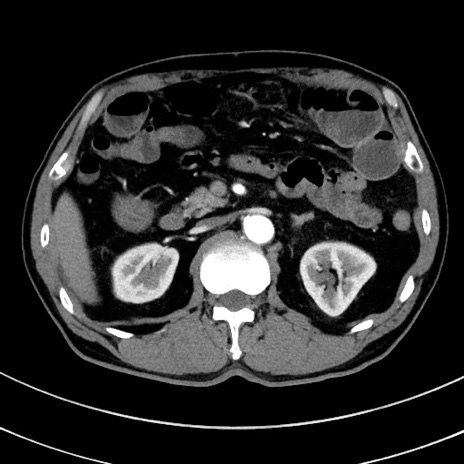

症例8(横断像)

【症例】 60歳代男性

【主訴】 黒色吐物

【現病歴】 4日前から嘔気自覚、2日前の朝食後にも嘔気あり、自分で手で嘔吐反射起こし嘔吐したところ血が混ざっていたため受診。

【既往歴】 5年前汎発性腹膜炎を伴う急性虫垂炎で手術、高血圧、前立腺肥大症、高脂血症

【身体所見】 腹部正中に手術癩痕あり 腹部平坦・軟圧痛なし膨満感あり

【データ】WBC 8400、CRP 4.54